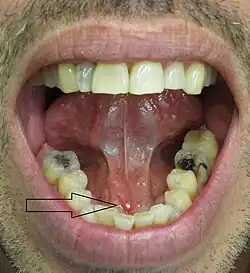

- Palpable hard lump, if the stone is located near the end of the duct.[1][3] If the stone is near the submandibular duct orifice, the lump may be felt under the tongue.

- Erythema (redness) of the floor of the mouth (infection).[3]

- Pus discharging from the duct (infection).[3]